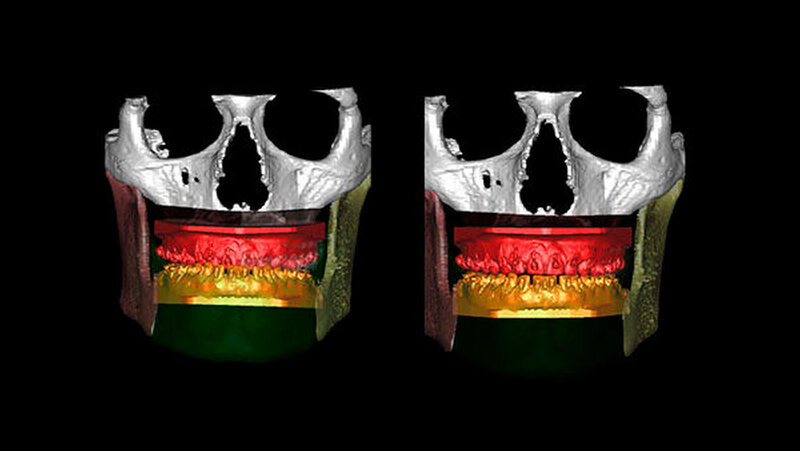

Die Abbildungen 1 und 2 zeigen die klinische Situation bei Erstvorstellung: Der Unterkiefer ist zu prominent. Der Oberkiefer und das Mittelgesicht liegen zurück. In der Front liegt ein umgekehrter Überbiss vor. Der Unterkiefer steht vor dem Oberkiefer. Das erschwert das Abbeißen und Kauen der Nahrung. Die Scans (siehe Abbildungen) dokumentieren, wie aufwendig die virtuelle Operationsplanung erfolgen musste.

Im Dezember 2014 führen die MKG-Chirurgen des Stuttgarter Katharinenhospitals die Umstellung des Ober- und Unterkiefers nach virtueller Chirurgie-Planung durch: Dabei trennen sie den Oberkiefer horizontal vom Gesichtsschädel ab (horizontale Osteotomie in der LeFort Ebene).

Hierzu wird von einem Schnitt im Mund der Oberkieferknochen freigelegt. Mit einer Säge kann ein gezielter Knochenschnitt erfolgen, und nach Präparation wird der Zahn tragende Abschnitt des Oberkiefers vom restlichen Gesichtsschädel gelöst.

Nun muss die Biss-Situation anhand des Computer gefertigten Biss-Schlüssels exakt eingestellt werden, bevor mit zwei Millimeter dicken Osteosyntheseplatten aus Titan der Knochen in der neuen Position mit Hilfe von Titanschrauben fixiert wird. Im Unterkiefer erfolgt die Schnittführung im Zahnfleisch hinter dem letzten Backenzahn beidseits. Nun wird der Unterkiefer mit spezieller Technik durchtrennt. Dies erlaubt eine Verschiebung der Zahn tragenden Basis vom Gelenk tragenden Knochenabschnitt des Unterkiefers.

Bei der Präparation wird der im Unterkieferknochen verlaufende Nervus alveolaris sorgfältig geschont. Die neue Position wird mit einem zweiten Biss-Schlüssel, der die endgültige Biss-Situation einstellt, zugeordnet und mit Osteosyntheseplatten und -schrauben gesichert.